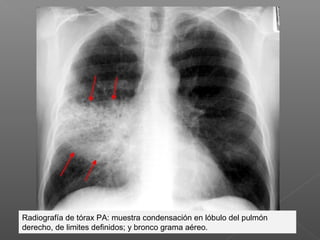

Radiografía de tórax PA: muestra condensación en lóbulo del pulmón

derecho, de limites definidos; y bronco grama aéreo.